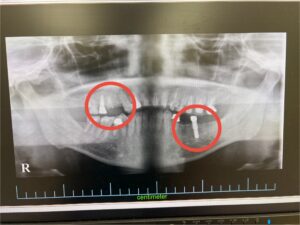

右上に1本、左下に2本の計3本のインプラントを同日に埋入する治療計画としました。(元々右上に1本、左下に1本の計2本はインプラントされてました。)

術前